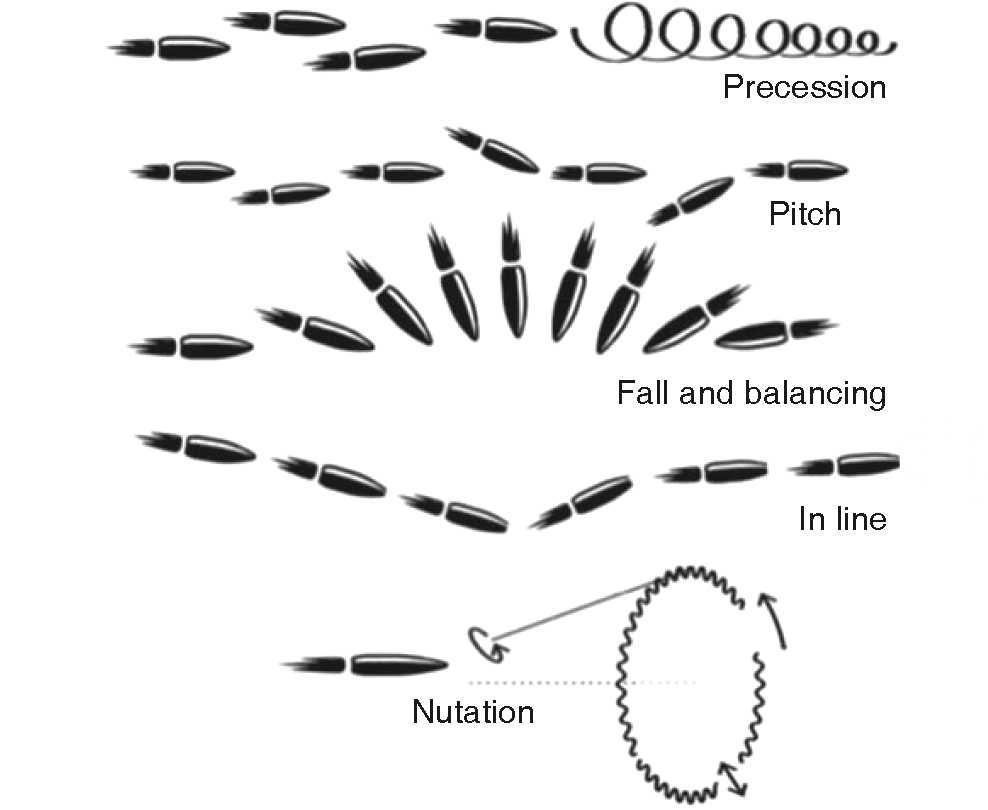

In these cases, the aim is to provide basic vital support, stabilize the patient and restore continuity, function and facial esthetics. For study purposes they are called ballistic wounds and are classified within penetrating trauma. Physics catalogues a projectile's movements into three parts: interior (within the barrel), exterior (from exit to impact), terminal (penetration into solid objects). The following displacement patterns can be observed: Precession, fall and balancing, pitching, in line and nutation (Figure 1).3,4 There is no universal agreement to classify them according to speed (velocity): US literature defines high speed to be found in the range 610-914 m/s, United Kingdom considers high speed anything over 335 m/s, Sherman and Parrish classify them in lesser than 330m/s (minor), between 330-600 m/s (medium) and in excess of 600 m/s (major) (Table II).2,5